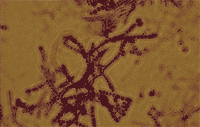

Zdjęcie w mikroskopie świetlnym, x 1000 |

Rys. 8 Termofilne promieniowce (Saccharopolyspora rectivirgula) (synonimy: Micropolyspora faeni, Faenia rectivirgula) |

Szczególne znaczenie jako przyczyna zawodowych chorób alergicznych mają termofilne promieniowce (Rys. 8), nitkowate bakterie uznawane za główną przyczynę najbardziej znanej formy (podjednostki) AZPP określanej jako „płuco rolnika”, lub „płuco farmera”.